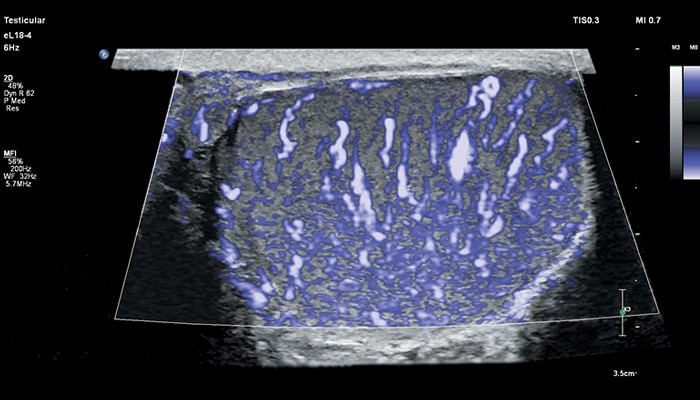

Линейный матричный датчик eL18-4 поддерживает режим высокочувствительной визуализации кровотока (Philips MicroFlow Imaging), новый запатентованный метод, который обеспечивает инновационный подход к оценке сосудистого русла. Визуализация MicroFlow преодолевает многие барьеры, связанные с традиционными методами обнаружения кровотока в малых сосудах, обеспечивая высокое разрешение при минимальных артефактах.

Метод MicroFlow Imaging поддерживает высокую частоту кадров и качество изображения, применяет инновационные методы сокращения артефактов. Варианты вычитания 2D-изображений, смешивания и параллельного отображения обеспечивают превосходную визуализацию в различных клинических случаях.

• Визуализация микрокровотока с высоким разрешением (MFI)